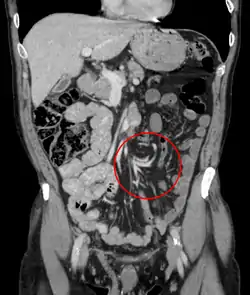

![]() تصوير مقطعي محوسب إكليلي لمنطقة البطن يظهر انفتال كما يظهر على شكل التواء بكتلة الأمعاء تصوير مقطعي محوسب إكليلي لمنطقة البطن يظهر انفتال كما يظهر على شكل التواء بكتلة الأمعاء | |

تتضمن عوامل الخطر العيب الخلقي المعروف بسوء الدوران المعوي، والقولون المتضخم، ومرض هيرشسبرونغ، والحمل، والالتصاقات البطنية. يمكن للإمساك طويل الأمد والحمية الغذائية مرتفعة الألياف أن تزيد الخطر.[3] يعد القولون السيني الجزء الأكثر إصابةً والأعور ثاني أكثر الأجزاء إصابةً. يصيب عادةً الأمعاء الدقيقة أكثر عند الأطفال.[4] يمكن أن تتأثر المعدة أيضًا.[5] يُشخص نموذجيًا عن طريق التصوير الطبي مثل الأشعة السينية، أو الحقن بالباريوم، أو التصوير المقطعي المحوسب.